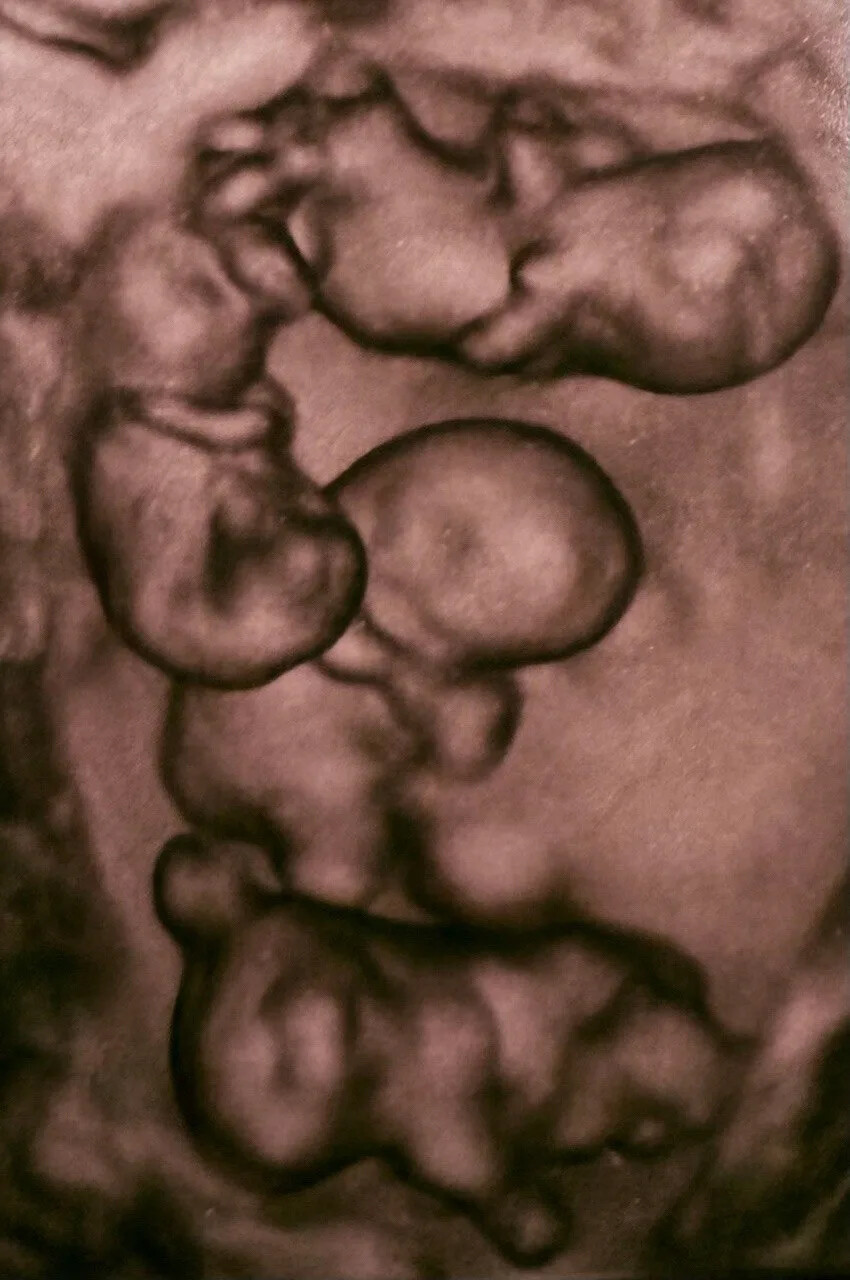

По информации РИА Новости, вес новорожденных девочек составляет от 1,36 до 1,64 килограмма, рост – от 37 до 41 сантиметра. По оценке специалистов родильного дома, это прекрасные показатели для рождения на таком сроке.

«Для 32-й недели беременности это отличный результат, который стал возможен благодаря правильной тактике ведения мамы на дородовом отделении и мастерству врачей», – добавили в медучреждении.